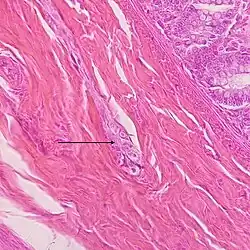

O plexo submucoso ou plexo de Meissner faz parte do sistema nervoso entérico. É formado por uma cadeia de neurônios interconectados que controlam principalmente a secreção gastrointestinal e o fluxo sanguíneo local. Situa-se na camada submucosa em todo o trato gastrointestinal . Suas funções estão ligadas à região mais interna da parede do intestino, controlando a secreção local, absorção, e contração do músculo submucoso, que é capaz de formar pregas na parede.[1]